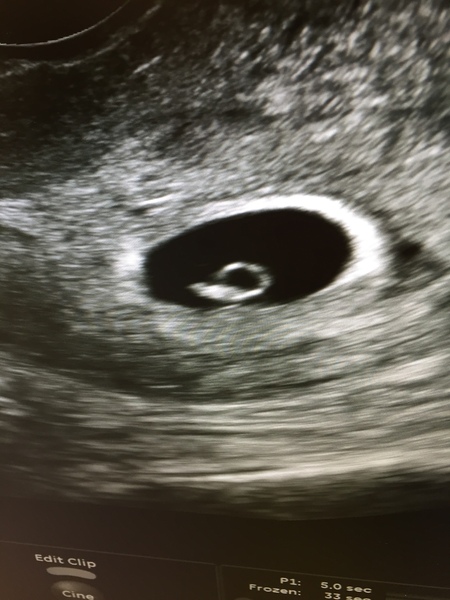

Zaberwocky · 12/04/2017 15:24

Well 😂 After several hours, I present to you, what appears to be a snail.